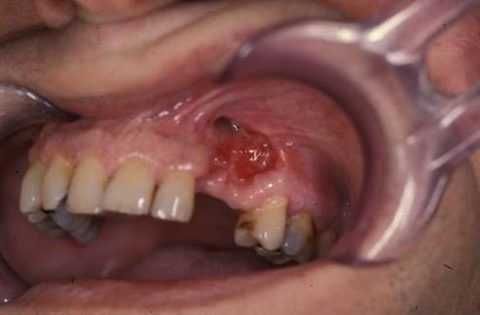

В некоторых случаях болезнь может провоцировать острая травма челюстно-лицевой области. Травматический остеомиелит челюстей при переломе считается достаточно редкостным осложнением и является следствием нагноения краев травмы.

![Постравматический остеомиелит нижней челюсти]()